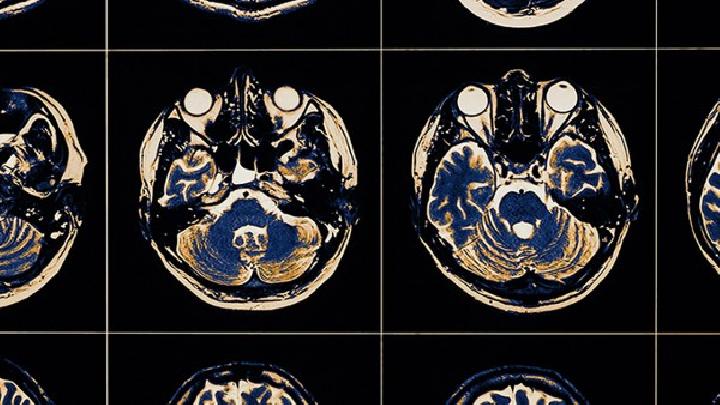

加利福尼亚脑炎容易与哪些疾病混淆?

本病需要鉴别西方马脑炎、

单纯疱疹性脑炎

乙脑

等。